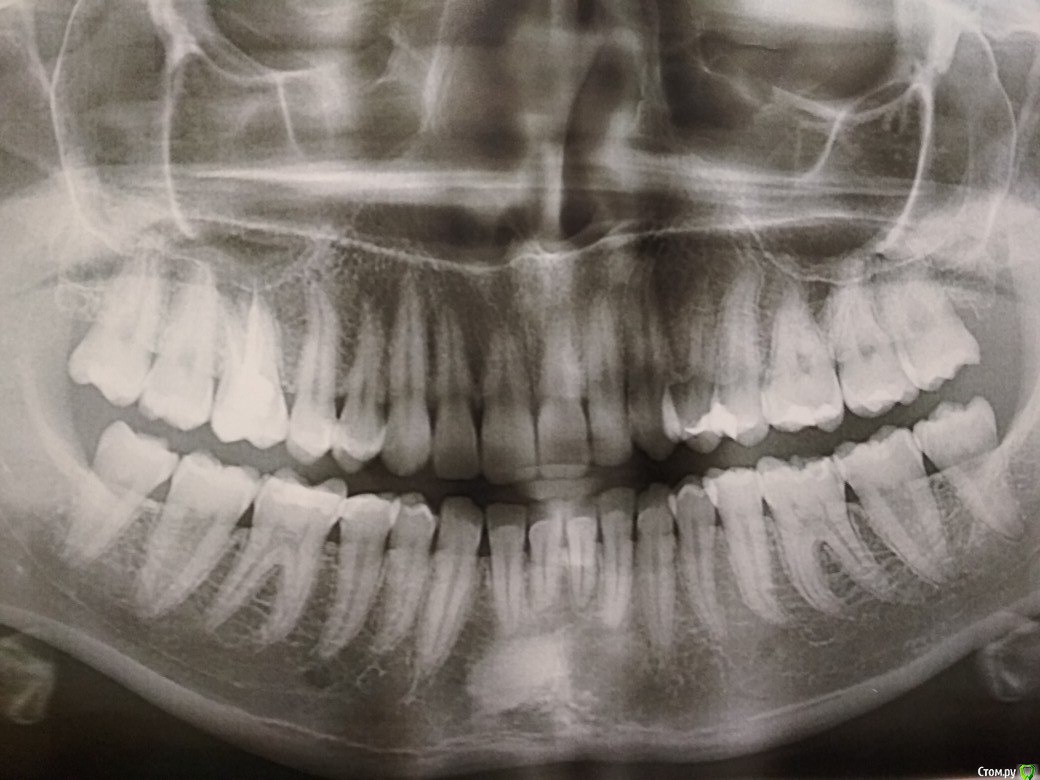

Стерхова Юлия Опубликовано 4 января, 2018 Поделиться Опубликовано 4 января, 2018 Здравствуйте! Достаточно давно, около 6-7 лет назад в связи с образованием глубокого кариеса мне была депульпирована верхняя правая шестёрка. Зуб не беспокоил все это время до декабря 2017 года. В один момент зуб начал периодически побаливать, в первый визит стоматолог предположил, что дело в оголившейся шейке. Через пару недель зуб перестал ныть, но появилась сильная боль при надкусывании: челюсть в покое 15-20 минут - зубы смыкаются - сильная боль. Так же при пережевывании чего-то твёрдого. С такой жалобой обратилась к тому же врачу. В клинике сделал прицельный снимок (на руки не выдали), доктор сказал все хорошо, каналы в нормальном состоянии, болит на погоду и должно пройти. Прошел месяц, боль осталась, я сделала панорамный снимок, чтобы исключить проблемы с соседними зубами, обратилась к другому врачу. Новый врач выписала ибупрофен 5 дней, тоже сказала что на погоду болит. Курс сегодня закончился, боль сохраняется в ночное время, днём почти отсутствует. Врач предложила перепломбировать каналы, если противовоспалительное не поможет, хотя на снимке нет показаний для этого. Вопрос в следующем: стоит ли соглашаться на перепломбировку или возможны иные методы лечения? Может, что-та на снимке все же не так? Снимок прикрепляю. Ссылка на комментарий

dok1 Опубликовано 4 января, 2018 Поделиться Опубликовано 4 января, 2018 Снимок неинформативен. Но раз болит - надо перелечивать. Просто так болеть не будет. Ссылка на комментарий

Стерхова Юлия Опубликовано 5 января, 2018 Автор Поделиться Опубликовано 5 января, 2018 Спасибо за ответ! Снимок к сожалению отпечатан на фотобумаге, иначе не получилось его сфотографировать. Ссылка на комментарий